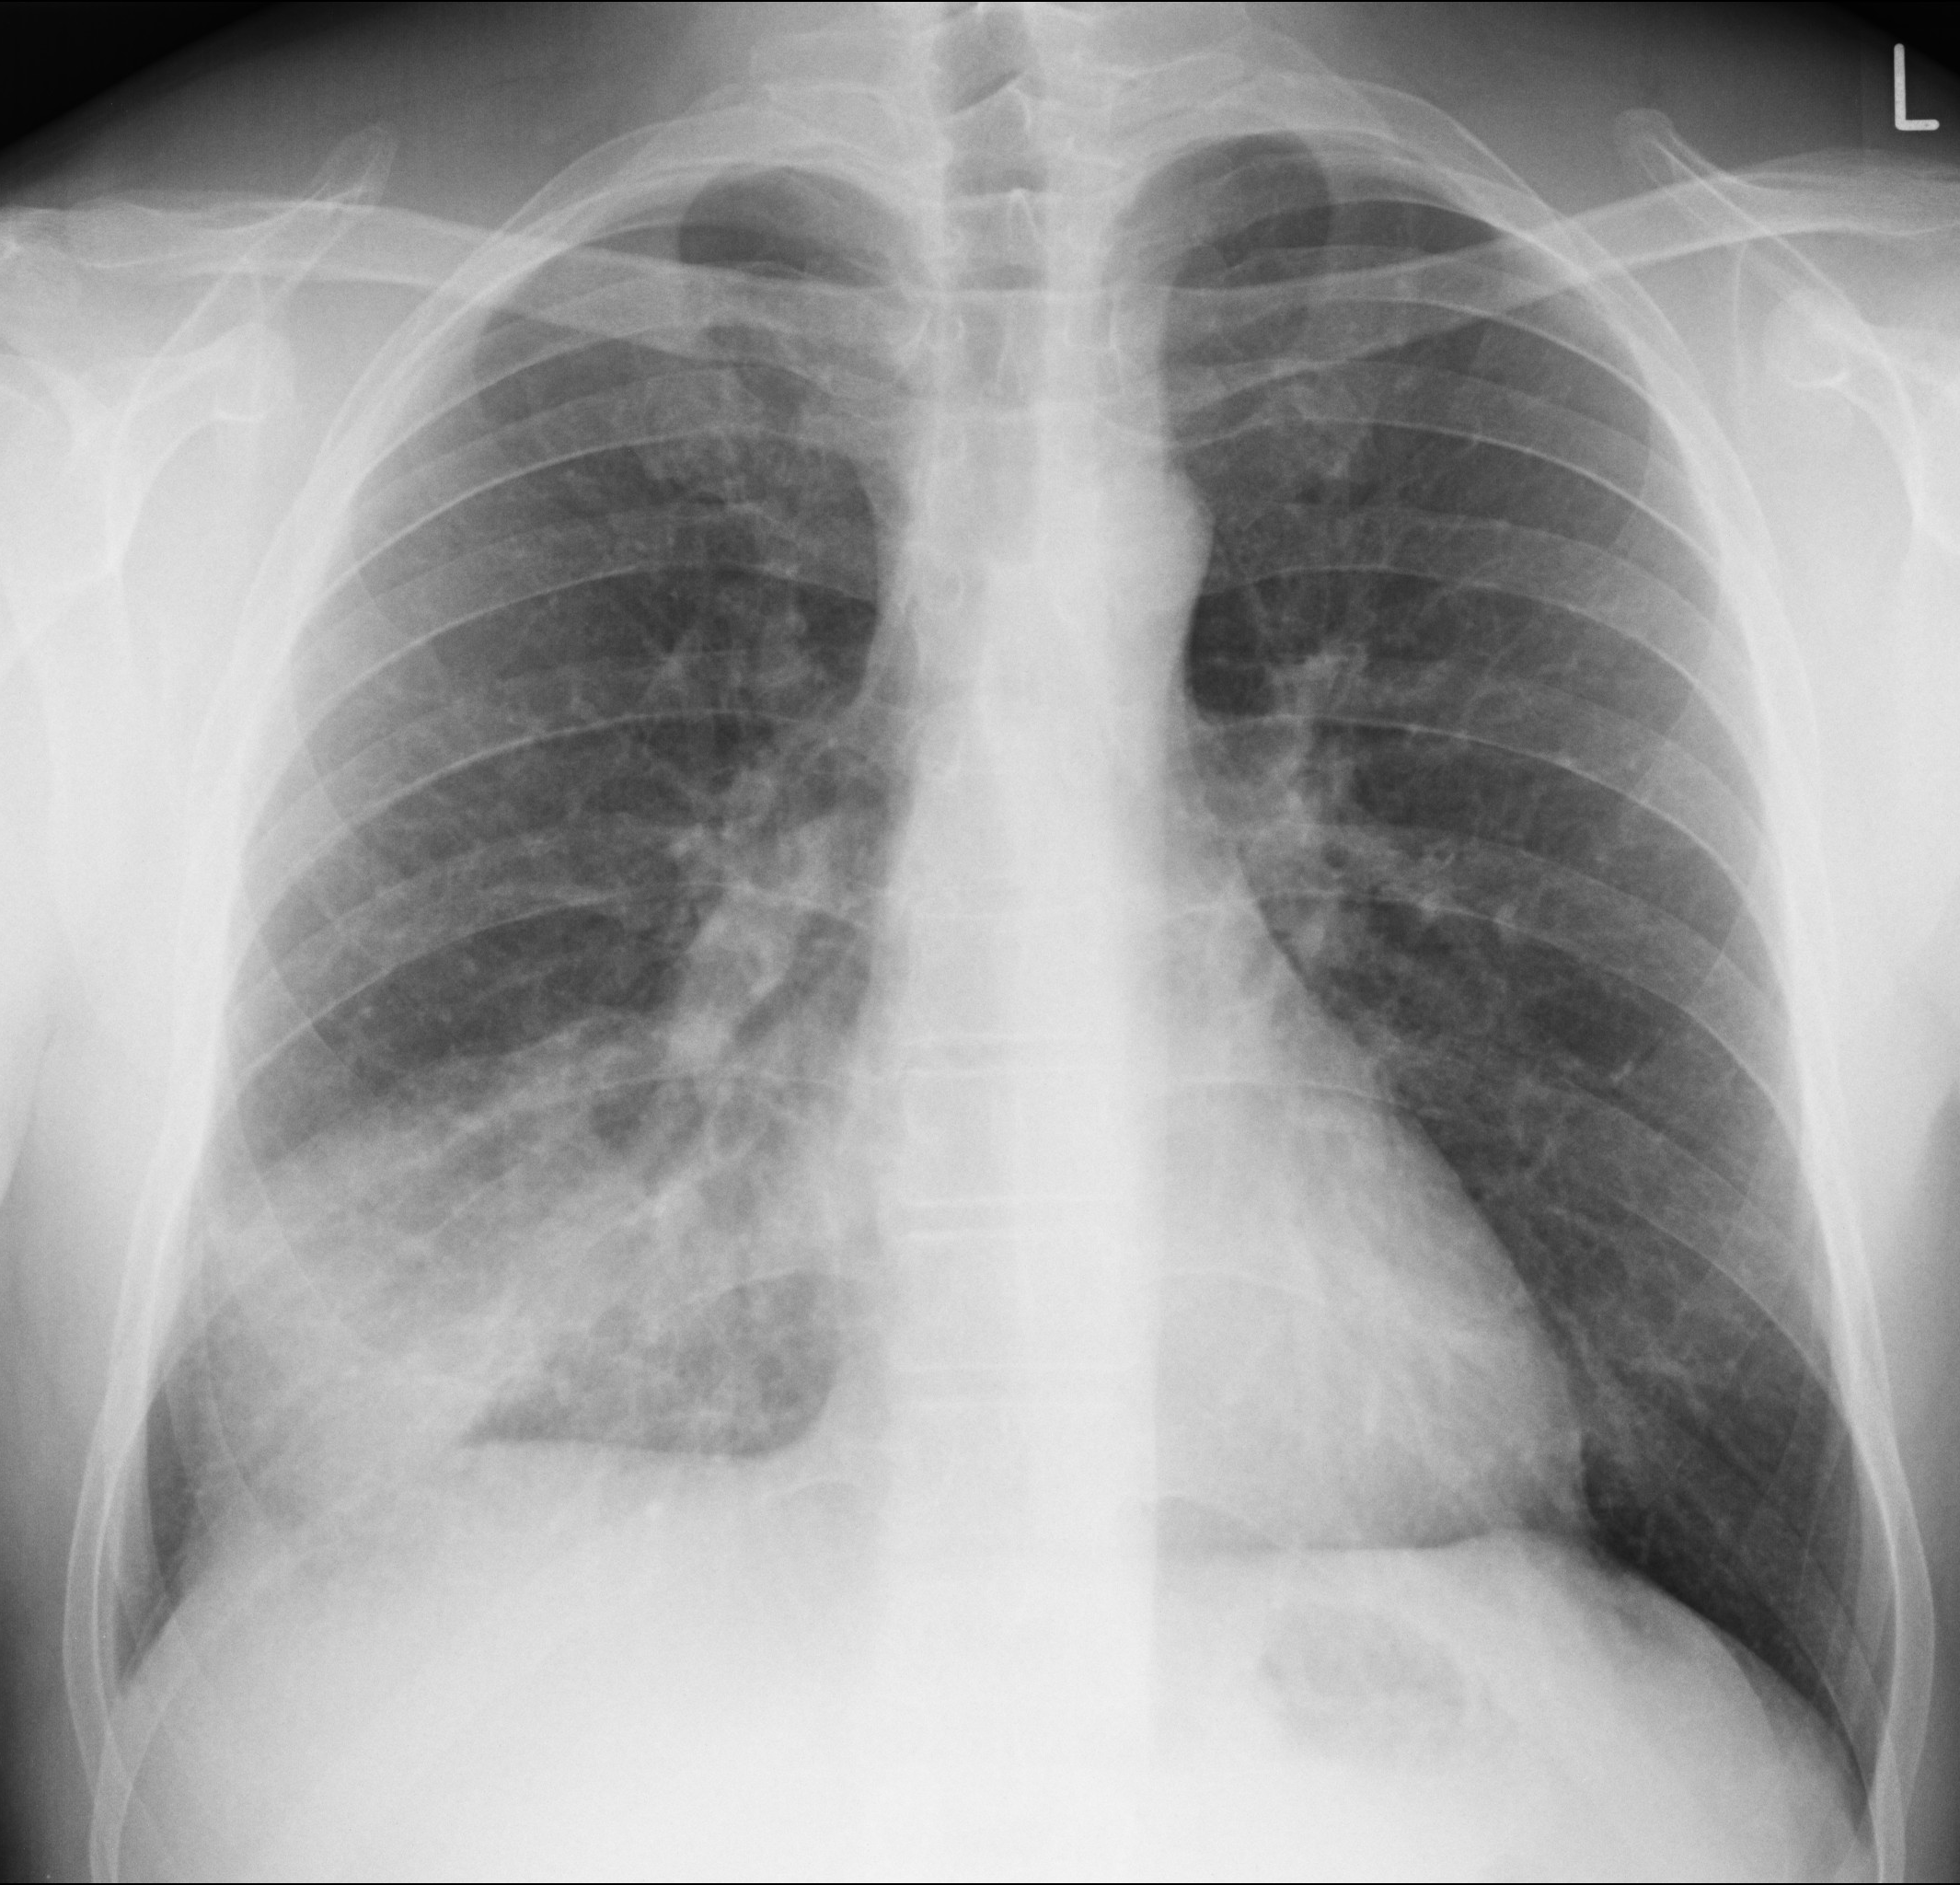

Você atende um paciente de 30 anos, do sexo masculino, com diagnóstico de tosse e febre há 2 dias. A tosse é produtiva, acompanhada de uma febre de 39ºC. Há um dia houve piora do quadro, com dispnéia, mal-estar e inapetência.

O exame físico demonstra que o paciente está dispneico, e febril, com estertores crepitantes na base pulmonar direita. Os exames laboratoriais demonstram uma leucocitose, com desvio.

Frente ao caso ilutrado, já formulamos uma hipótese diagnóstica: pneumonia.

Já temos em mente também o exame a ser solicitado - um raio-X de tórax.

A radiografia acima demonstra um infiltrado de aspecto alveolar, pelo seu aspecto algodonoso, localizado no lobo médio. Este padrão alveolar basicamente confirma a nossa hipótese diagnóstica de pneumonia.

Temos neste primeiro caso, portanto, um exemplo de como um exame radiológico pode te ajudar a confirmar uma hipótese diagnóstica.